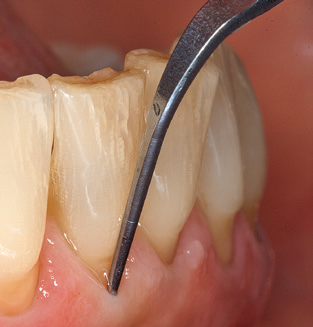

Naturalmente, anche i consigli di lavoro per la pulizia delle superfici degli impianti sono indispensabili per SPT nei pazienti dotati di impianti. L'inserto per la pulizia dell'impianto in questo casoi è caratterizzato dal suo design affusolato ed esagonale. Questo design consente una penetrazione leggera e atraumatica nella tasca perimplantare e mostra buone prestazioni di pulizia (Fig. 7).